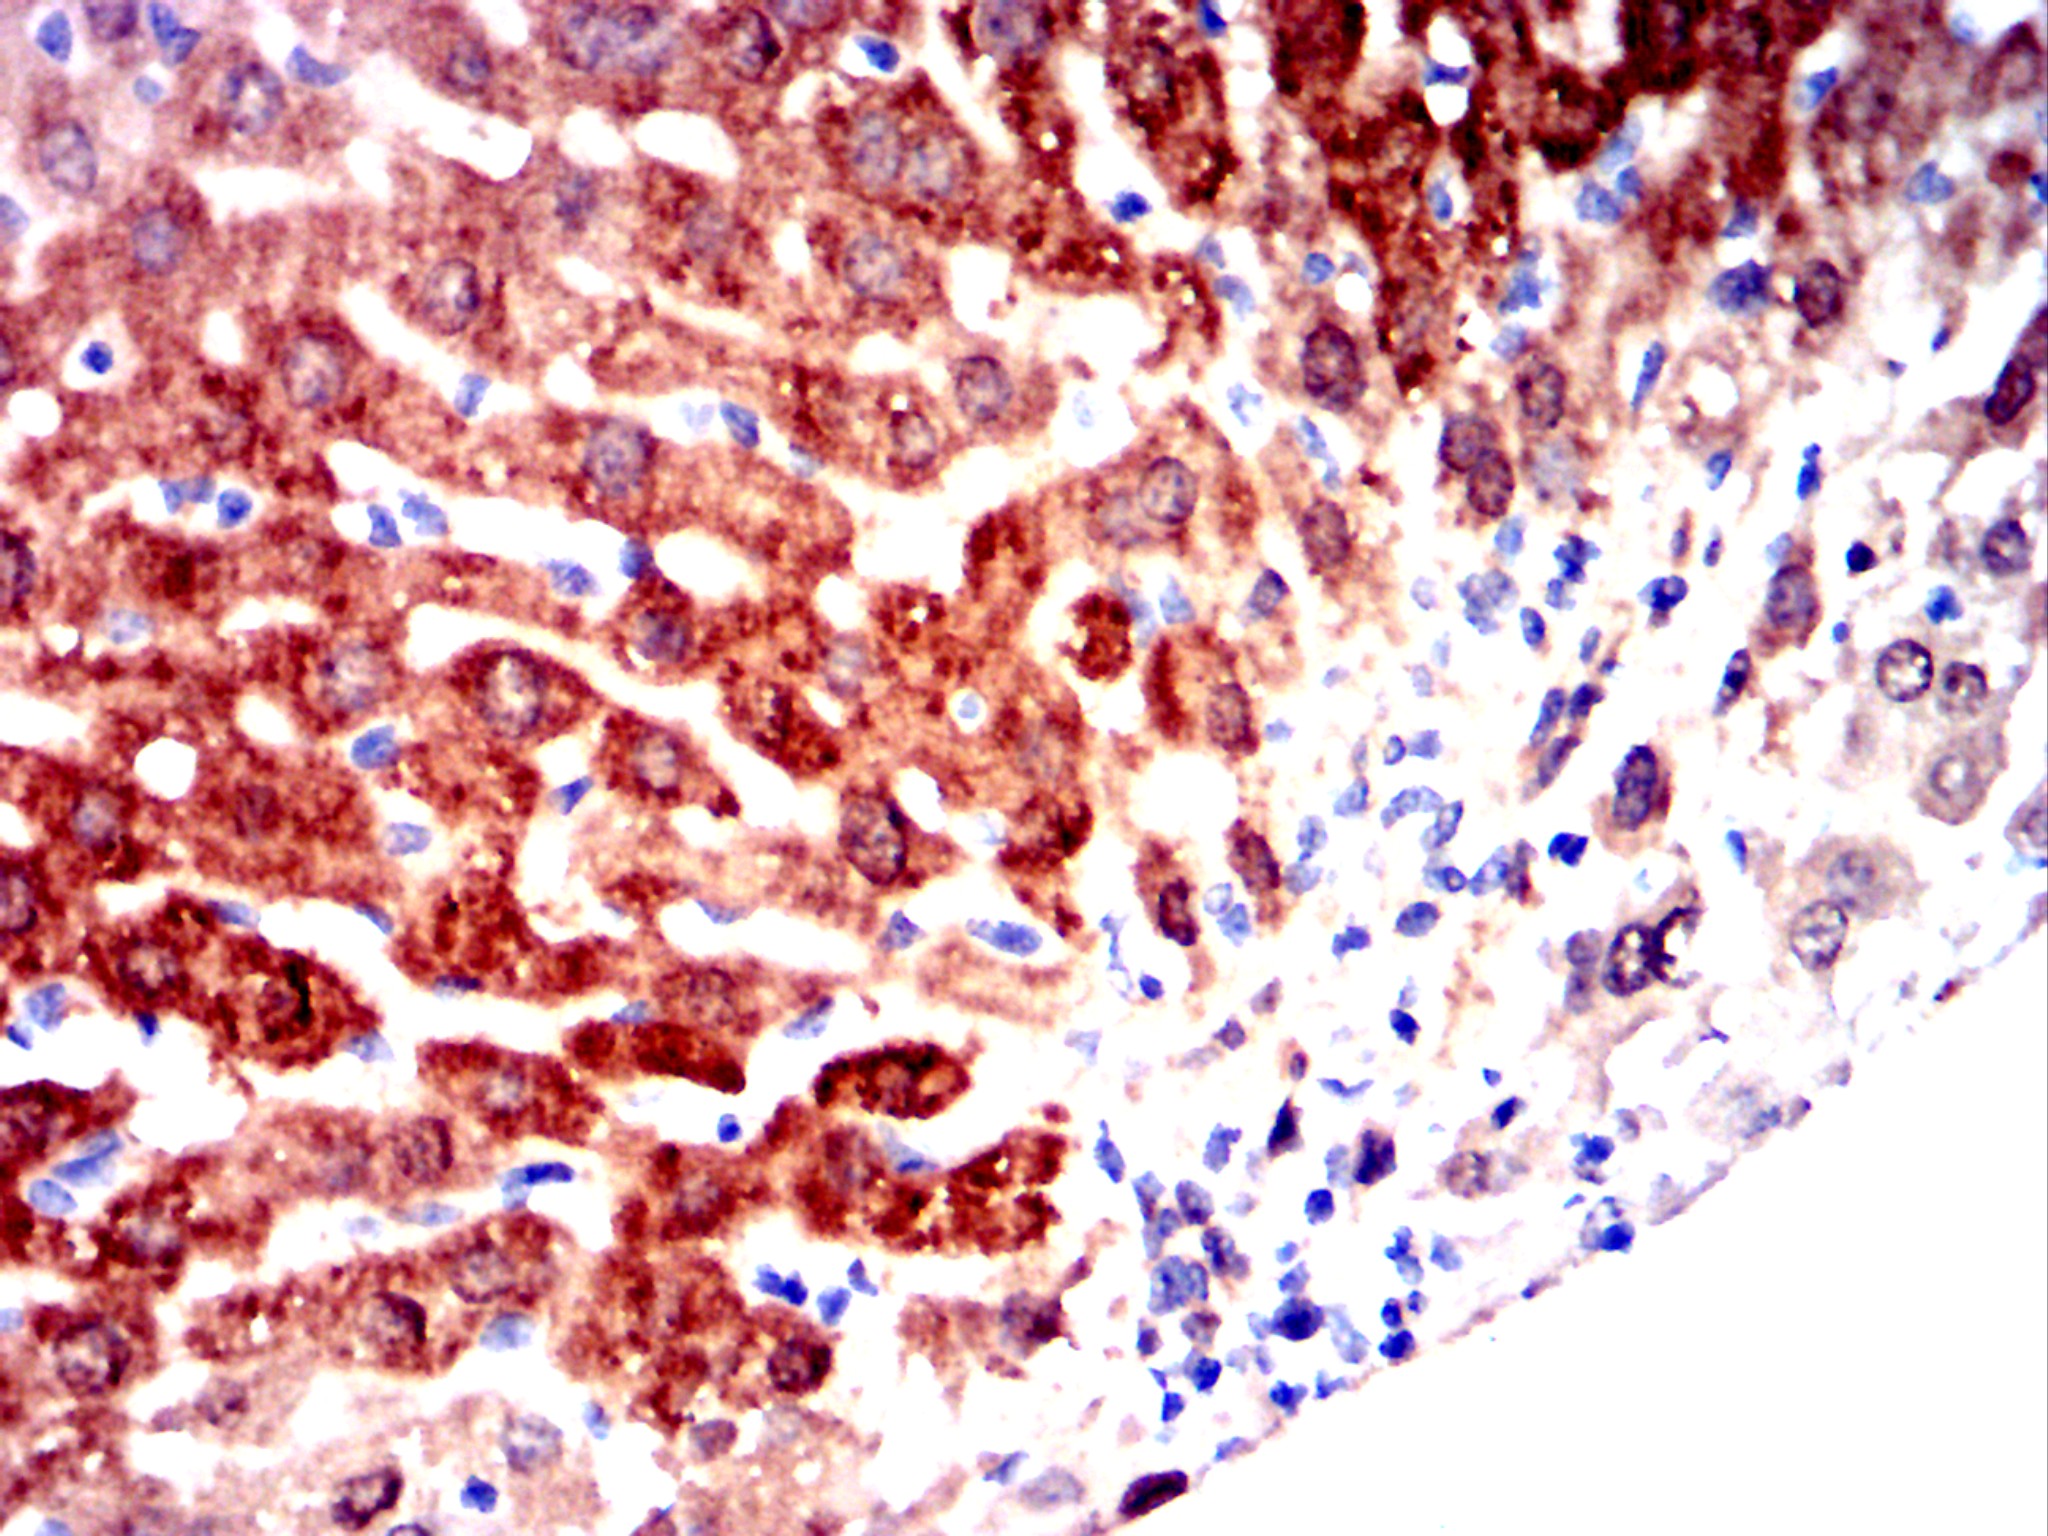

Immunohistochemical analysis of paraffin-embedded human lung cancer tissues using AKR1C1 mouse mAb with DAB stainin.

Immunohistochemical analysis of paraffin-embedded human stomach cancer tissues using AKR1C1 mouse mAb with DAB stainin.

Immunohistochemical analysis of paraffin-embedded human rrectal cancer tissues using AKR1C1 mouse mAb with DAB stainin.

Immunohistochemical analysis of paraffin-embedded mouse liver tissues using AKR1C1 mouse mAb with DAB staining.

Immunohistochemical analysis of paraffin-embedded rabbit liver tissues using AKR1C1 mouse mAb with DAB staining.

Immunohistochemical analysis of paraffin-embedded rabbit small intestine tissues using AKR1C1 mouse mAb with DAB staining.